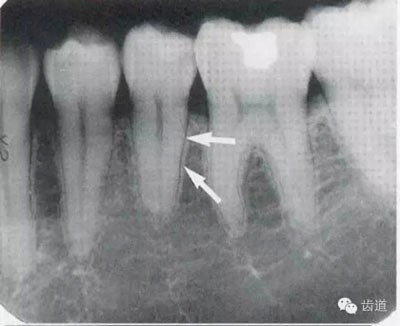

2)營養(yǎng)管:

常見于下頜前牙區(qū),在牙根之間的牙槽骨內(nèi)并與牙長軸平行的密度低的條狀影像。此為小血管進入牙槽突的影像。